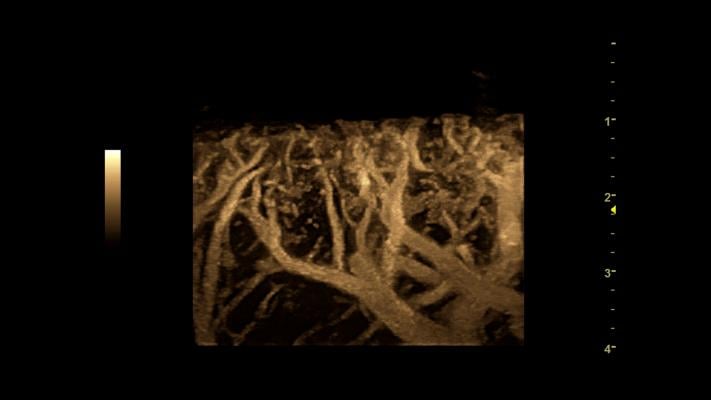

XDclear 2.0 optimizes the imaging from the pulse of the probe to each of its pixels and every step in between with up to 22 percent more contrast compared to the Logiq E9 with XDclear. Also, it has 99 percent improved spatial resolution and 170 percent more image information.

The E9 XDclear 2.0 system delivers high-quality images across a wide variety of cases, from the routine to the technically challenging. The XDclear technology enables exceptional penetration and sensitivity, according to the company, even with obese patients, while workflow tools help increase exam efficiency.